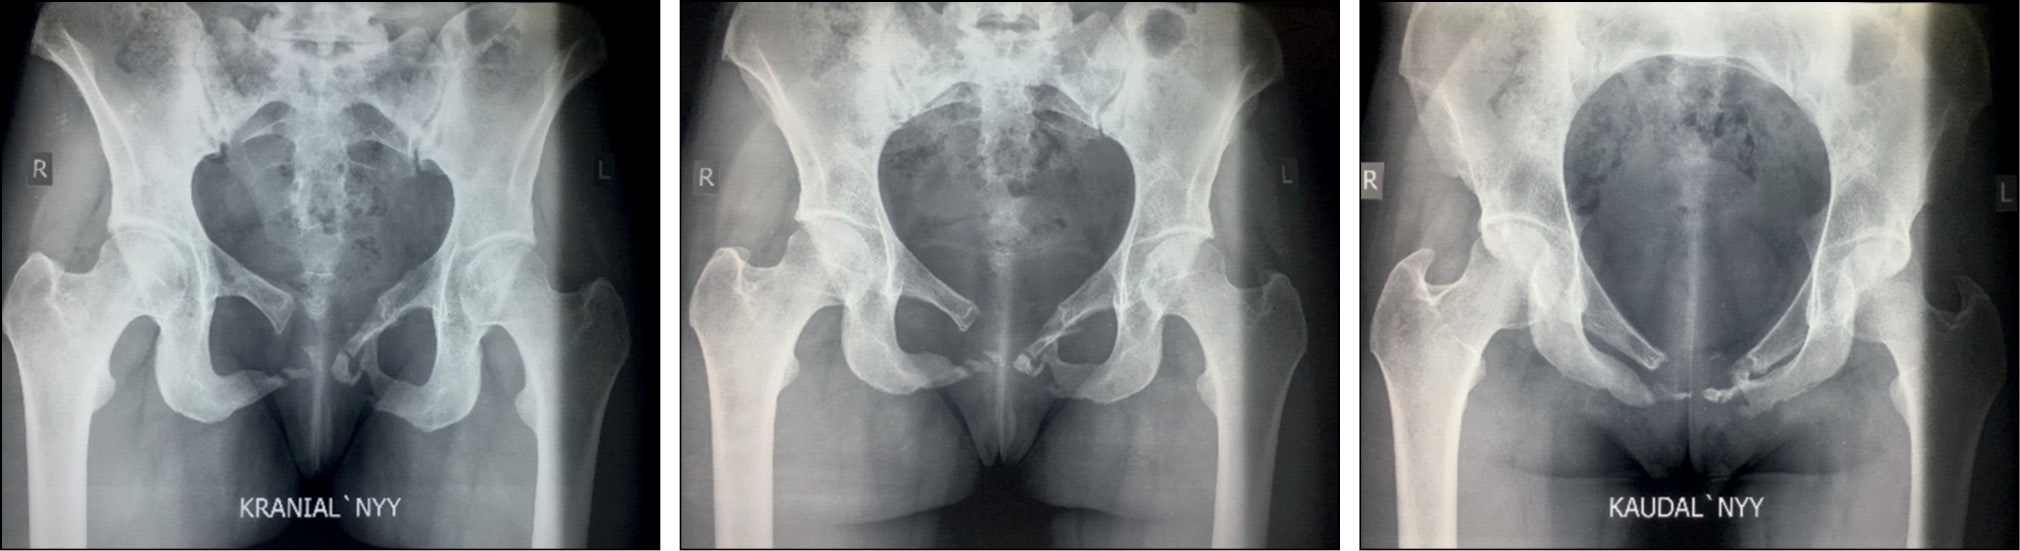

Отдалённый результат мы оценивали спустя 4 года после операции (рис. 5, 6) с использованием шкалы Majeed (табл. 1) [11]. Конечный функциональный результат составил 75 баллов. Пациентка результатом довольна, вышеизложенные жалобы отсутствуют.

Рис. 5. Рентгенограммы таза (краниальная, прямая и каудальная) пациентки С. через 4 года после операции.

Fig. 5. Radiographs of the pelvis (cranial, straight and caudal) of patient S. 4 years after surgery.